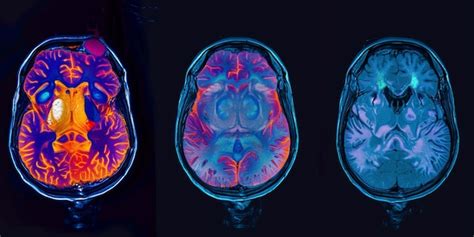

Los síntomas varían según las áreas afectadas e incluyen pérdida leve de memoria, dificultad de concentración, cambios sutiles en el estado de ánimo o comportamiento. El diagnóstico comienza con una evaluación clínica exhaustiva, incluyendo historia médica y familiar.

La localización y extensión de la atrofia se detectan mediante neuroimagen (TAC, resonancia magnética). Es crucial diferenciarla de otras afecciones con síntomas similares.